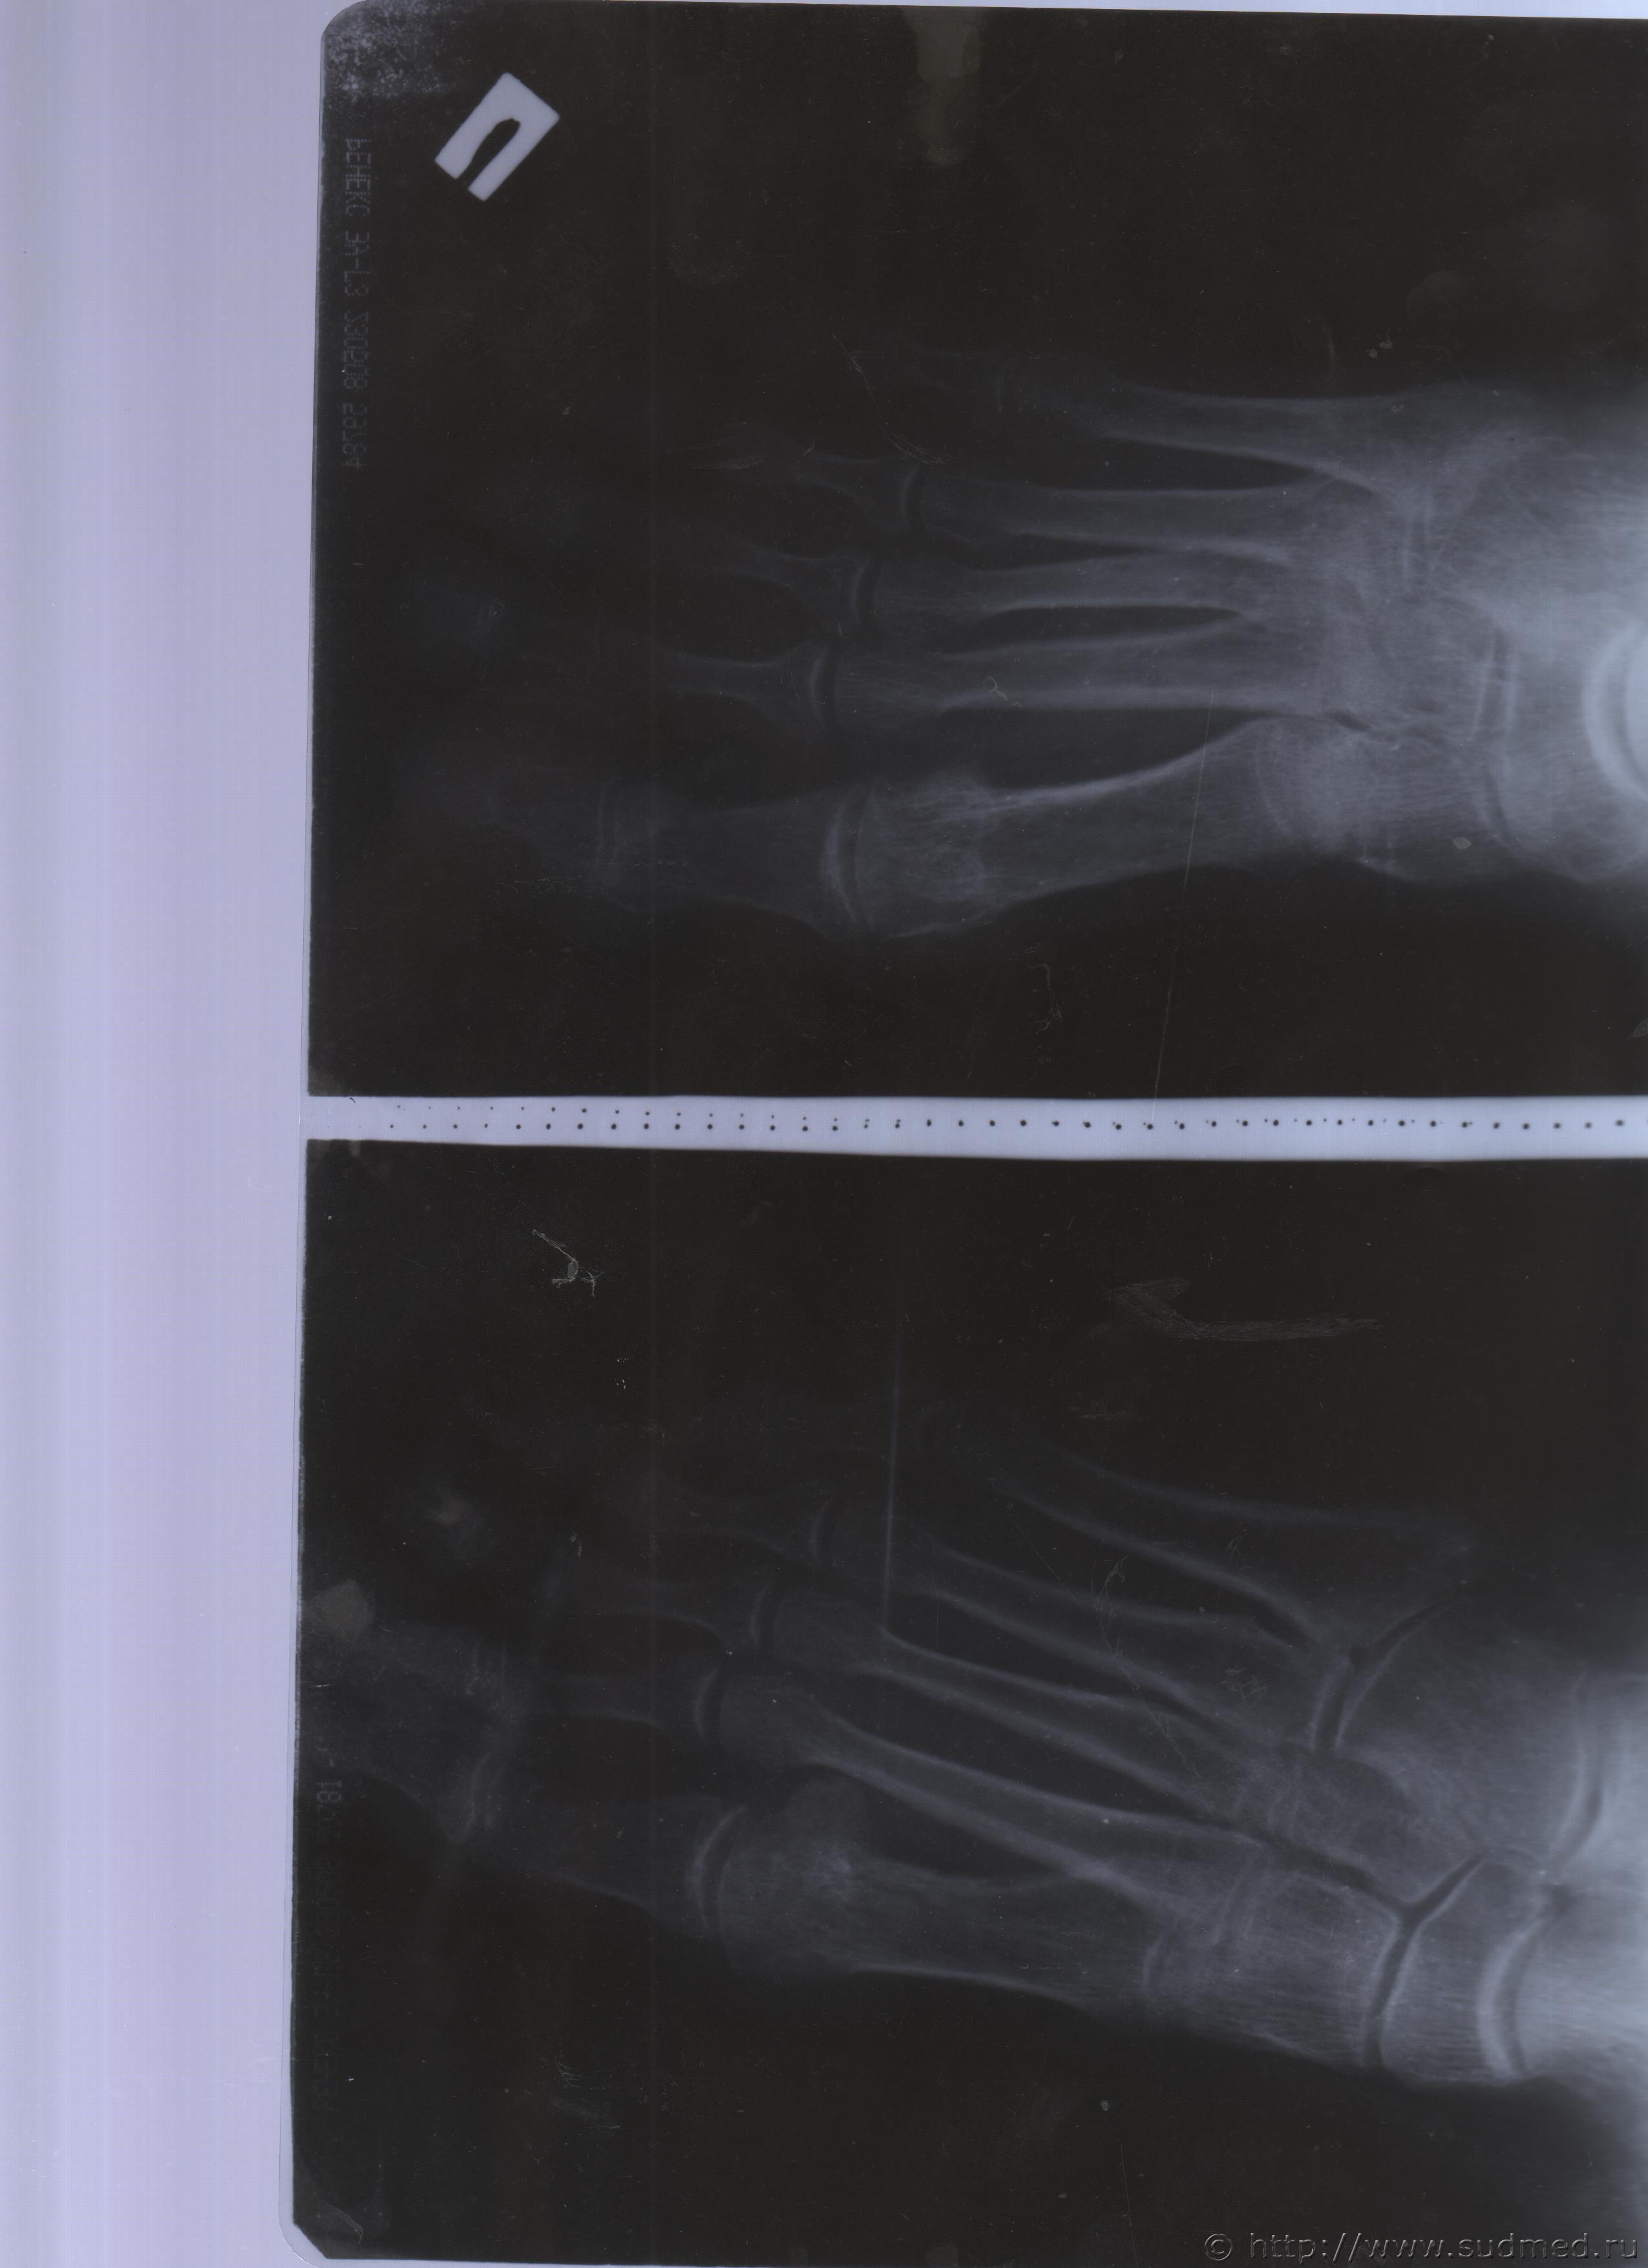

06.07.2015 г. при обращении в горбольницу мне выдали не описанный снимок( все рентгенологи были в отпуске) и справку № 4379 от 06.07.15 г. где диагноз: закрытый 2-х лодыжечный перелом правой голени без смещения. Копию справки прилагаю

За все 12 месяцев, что была на больничном, 8 раз делали снимки травмированной ноги и все заключения именно : «закрытый 2-х лодыжечный перелом правой голени без смещения».

Посмотрите, это снимки за 12 месяцев.

Уважаемая Татьяна! По представленным Вами снимкам ничего сказать нельзя: нет маркировки даты каждого снимка (поэтому, невозможно их сравнивать друг с другом и соотносить с датой травмы), исследование непосредственно пленок гораздо более информативно, чем анализ представленных изображений (детали костной структуры в зоне перелома практически не видны).

Рекомендую проконсультировать все эти снимки у высококвалифицированного рентгенолога. Далее - по ситуации, т.е. в зависимости от его мнения. В любом случае, есть формальные основания для назначения дополнительной экспертизы, т.к., судя по представленному Вами фрагменту заключения эксперта, на экспертизу не были предоставлены все мед.документы с данными о лечении предъявляемой травмы (Вы пишете, что рентгенограммы делались на протяжении 12 месяцев, полагаю, что Вы и врачами наблюдались в течение этого срока, т.е. велась мед.карта).